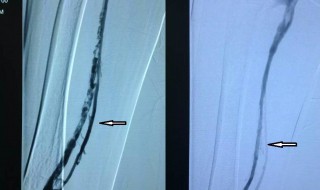

1、下肢血栓大多数是下肢血管的内膜受损和血流变慢造成的,一般情况下没有生命危险,如果下肢血栓脱落,可能会造成肺栓塞或者脑栓塞,就有生命危险。

2、对于你说的情况,建议尽早到正规医院检查,查清病因,可以使用溶栓的方法进行治疗。你要避免剧烈运动,清淡饮食,多喝水。